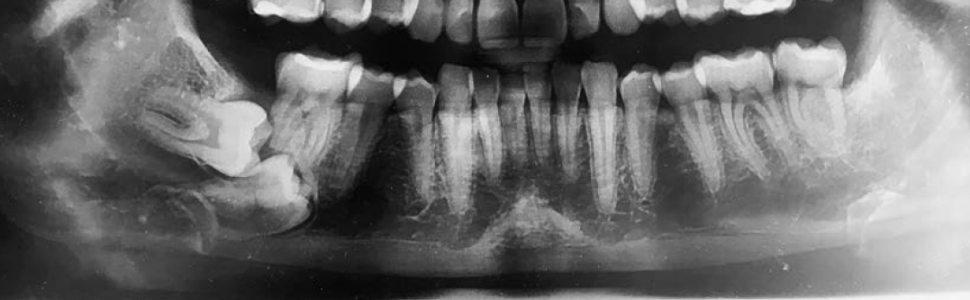

Zatrzymany ząb stały jest zębem, który nie wyrznął się w prawidłowej pozycji z powodu braku miejsca w łuku zębowym, niekorzystnego położenia lub innych czynników. Peterson podaje, że za ząb zatrzymany można uznać ząb, który nie pojawił się w jamie ustnej w określonym przez normy czasie. Wyrzynanie się zęba rozpoczyna się po uformowaniu ¾ długości jego korzeni. Zatrzymanie zębów jest zwykle diagnozowane po tym okresie i zazwyczaj przebiega bezobjawowo. I właśnie z tego powodu pacjenci zgłaszają się do leczenia później niż samo zaistnienie zjawiska.

A retained tooth is a tooth that has not erupted in the right position due to lack of space in the dental arch, its unfavourable location or other factors. Peterson states that a tooth that

has not appeared in the mouth within the time specified by the norm can be considered as a retained tooth. Teeth eruption begins after forming ¾ the length of its roots. Teeth retention is usually diagnosed after this period and usually occurs asymptomatically, therefore patients are seeking treatment very late or are not seeking treatment at all.